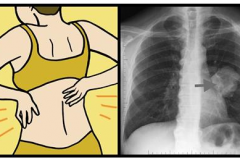

Թոքերի քաղցկեղի 8 նշան, որ յուրաքանչյուր կին պետք է իմանա